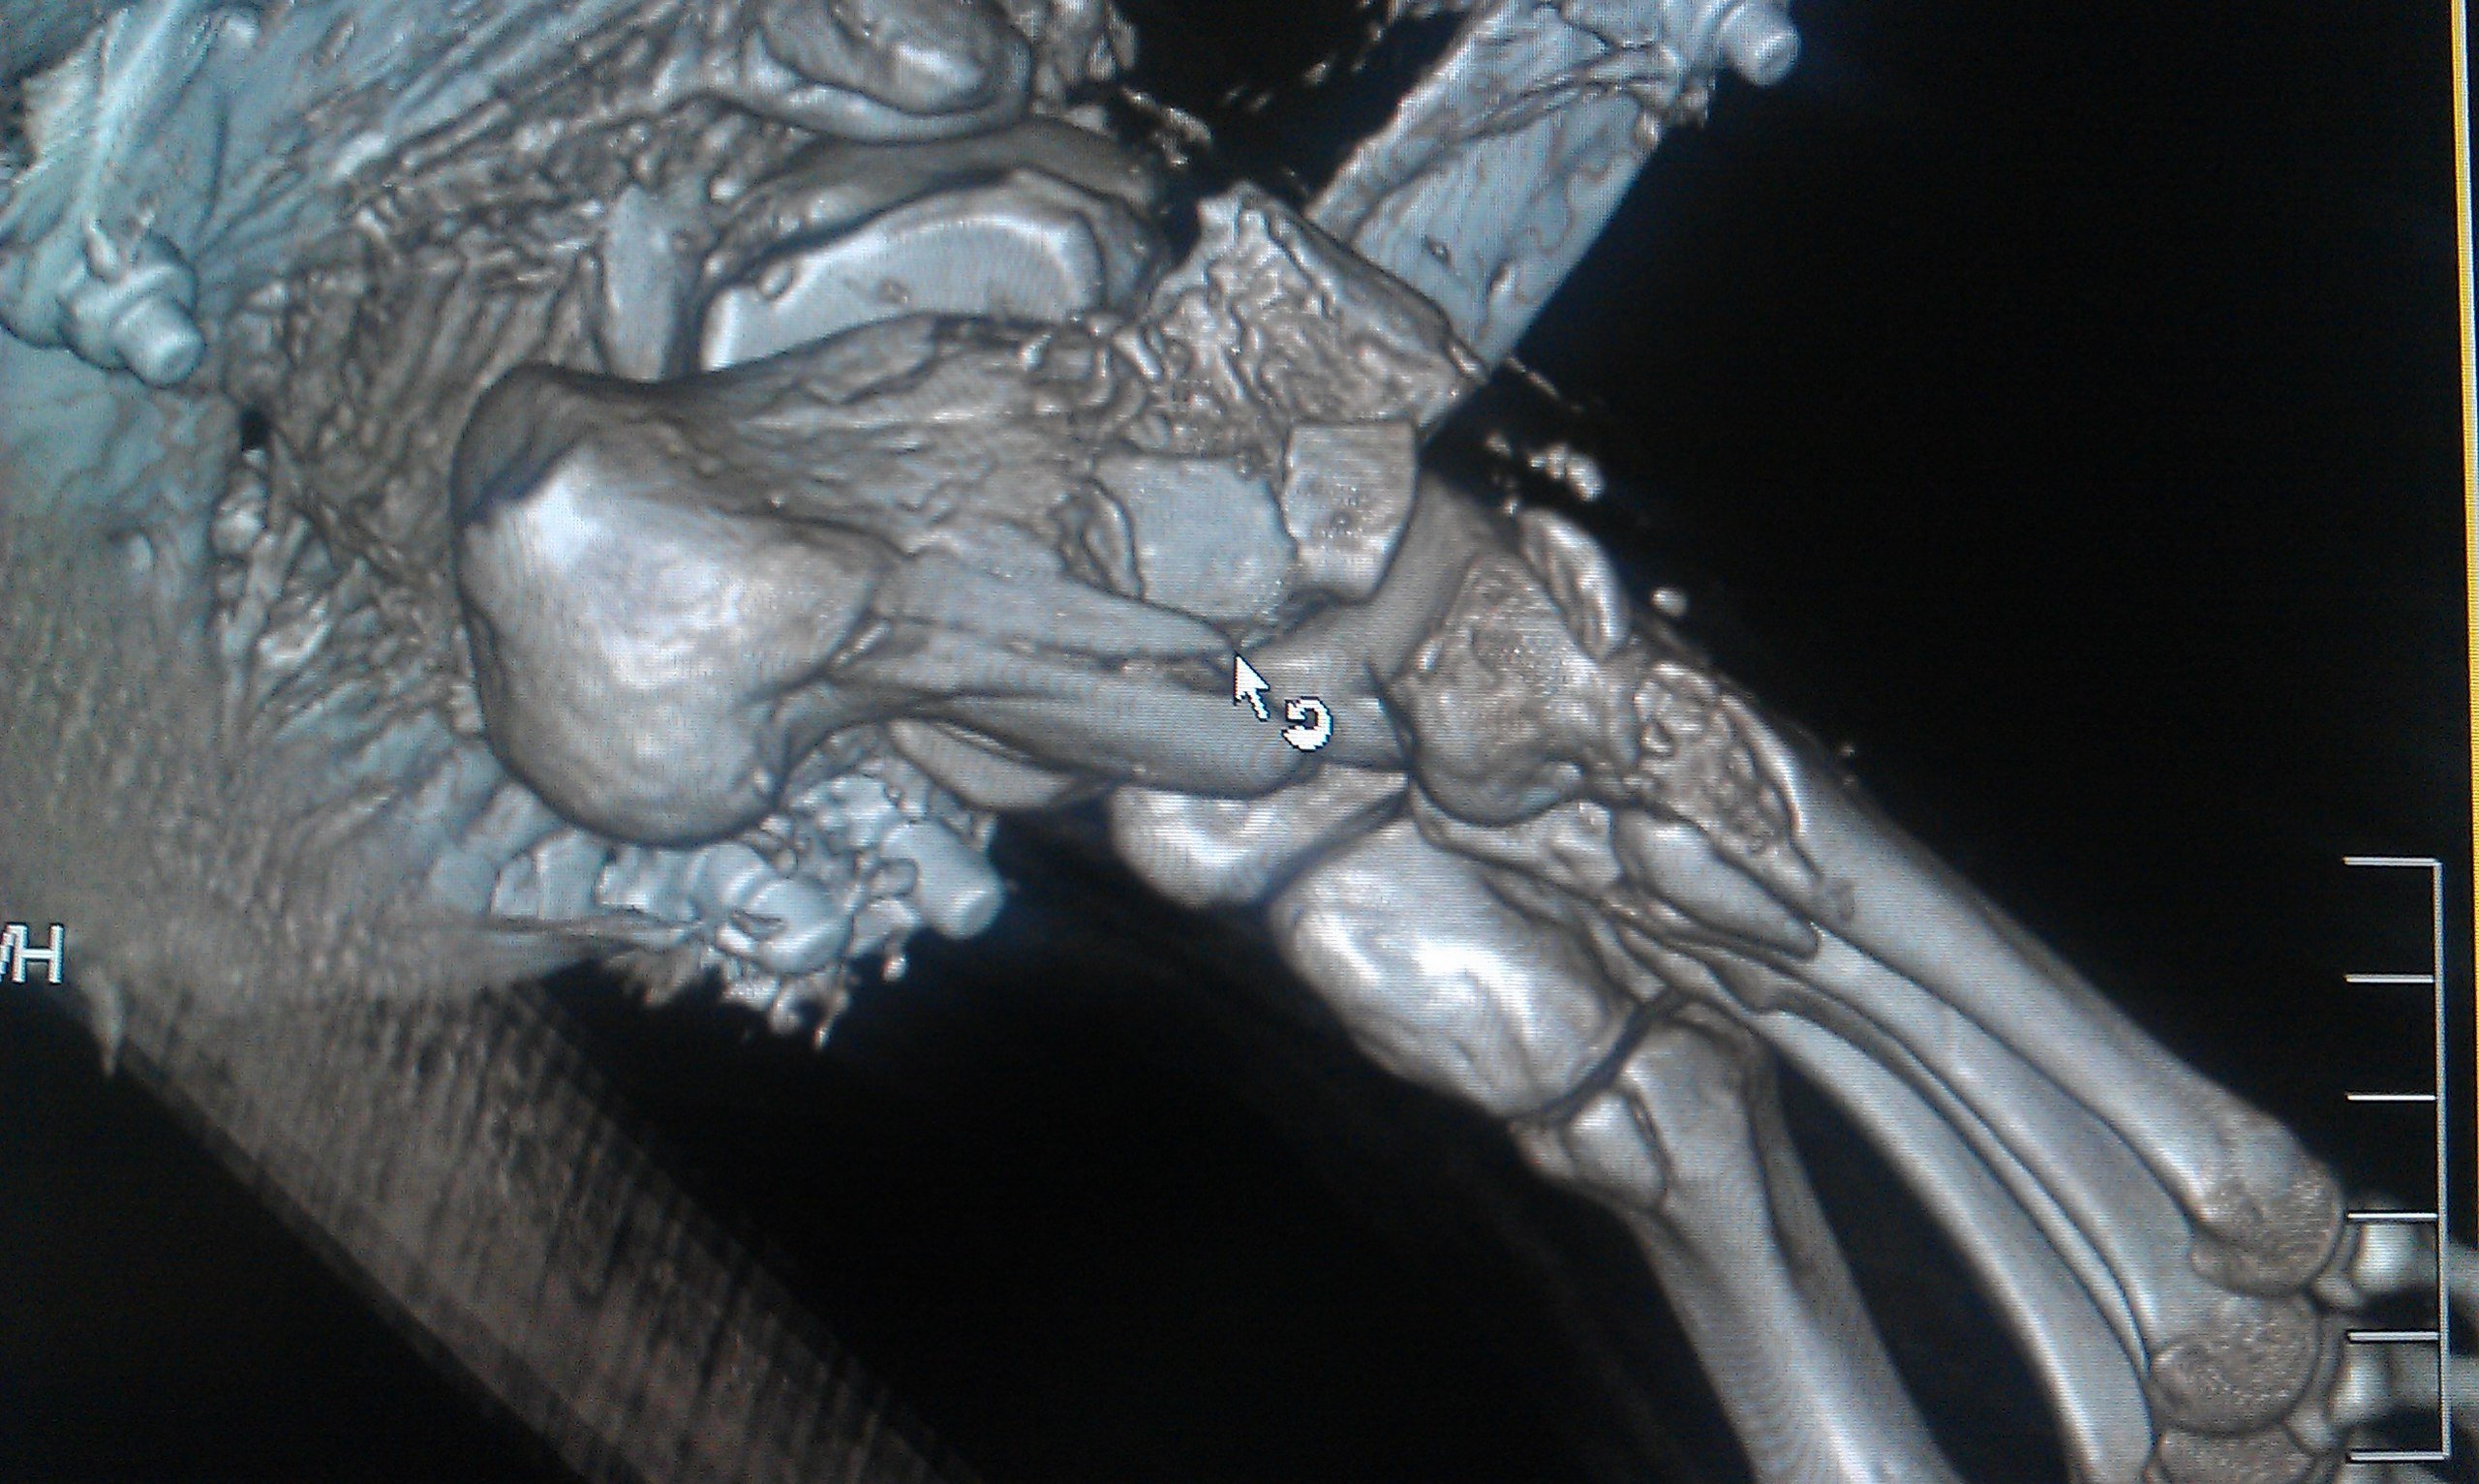

Эпикриз: Сочетанная травма. ЗЧМТ. Сотрясение головного мозга. Открытый многооскольчатый перелом обеих костей с/3 правой голени со смещением отломков. Открытый многооскольчатый перелом пяточной, ладьевидной, кубовидной кости, подвывих пяточной кости. Обширные рваные раны области правой стопы, правой голени.

было это еще 7 июня, но до сих пор, по прошествии двух операций ему не собрали все кости. Оказалосьь, что одну кость забыли на месте ДТП и теперь вместо нее требуется имплант. На одной ноге у него сейчас 18 переломов и 3 из них гниют, один из кусков кости встал поперёк, врачи опасаются её доставать или разворачивать, ибо можно занести ещё больше инфекции, если делать, то надо делать сразу всё комплексно, а пока приходится постоянно чистить, чтоб не было заражения, никакие обезболивающие уже не помогают, организм уже к ним адаптировался, и приходится терпеть эти боли. Нам же остается только медленно собирать деньги.